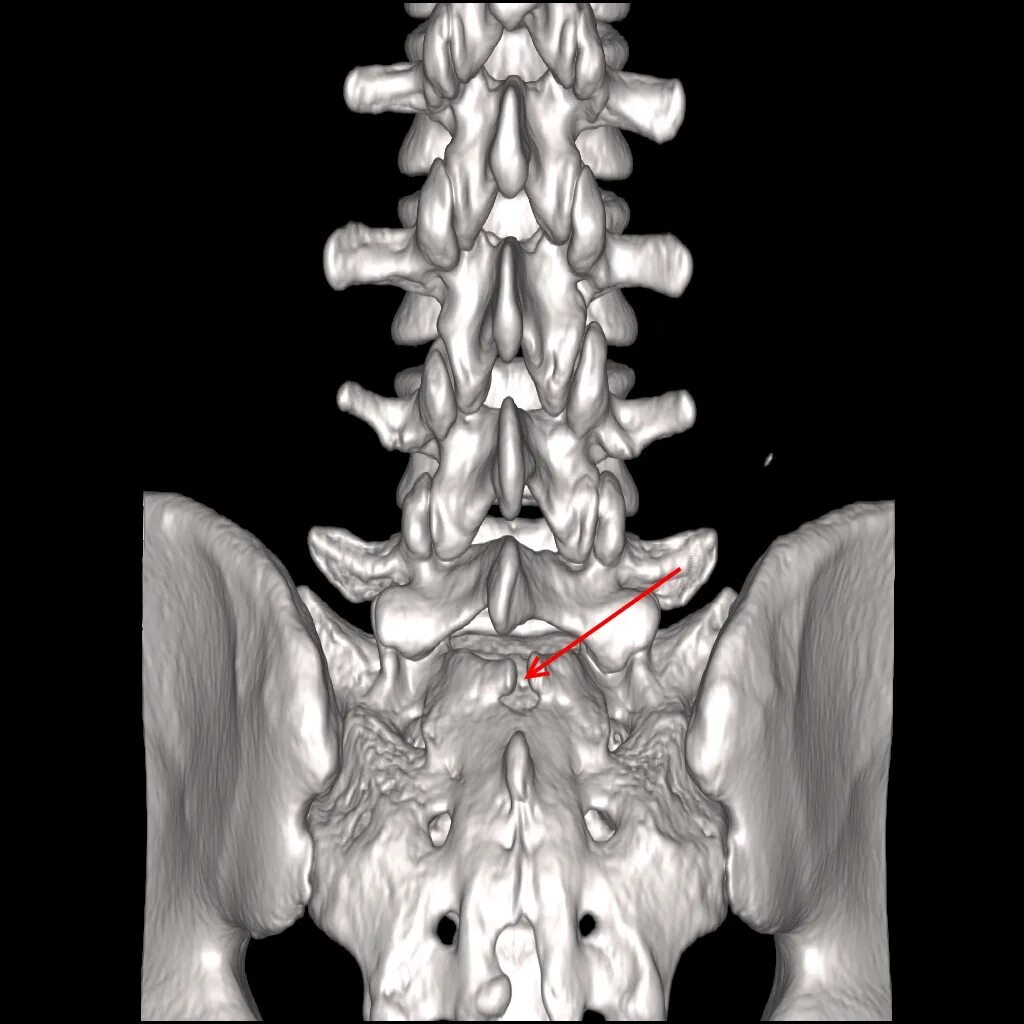

Поперечный перелом крестца. перелом боковых масс крестца. поперечный перелом крестца и копчика. классификация переломов креста.

Трансфораминальный перелом крестца. оскольчатый перелом крестца. перелом крестца s3 тип а2.

Крестец позвонки s1 s2 перелом. перелом боковой массы крестца справа.

Перелом крестцового позвонка кт. интрафораминальный перелом крестца.

Перелом боковых масс крестца. вертикальный перелом боковой массы крестца. классификация переломов креста. перелом латеральной части крестца.

Перелом боковых масс крестца. перелом латеральной части крестца.